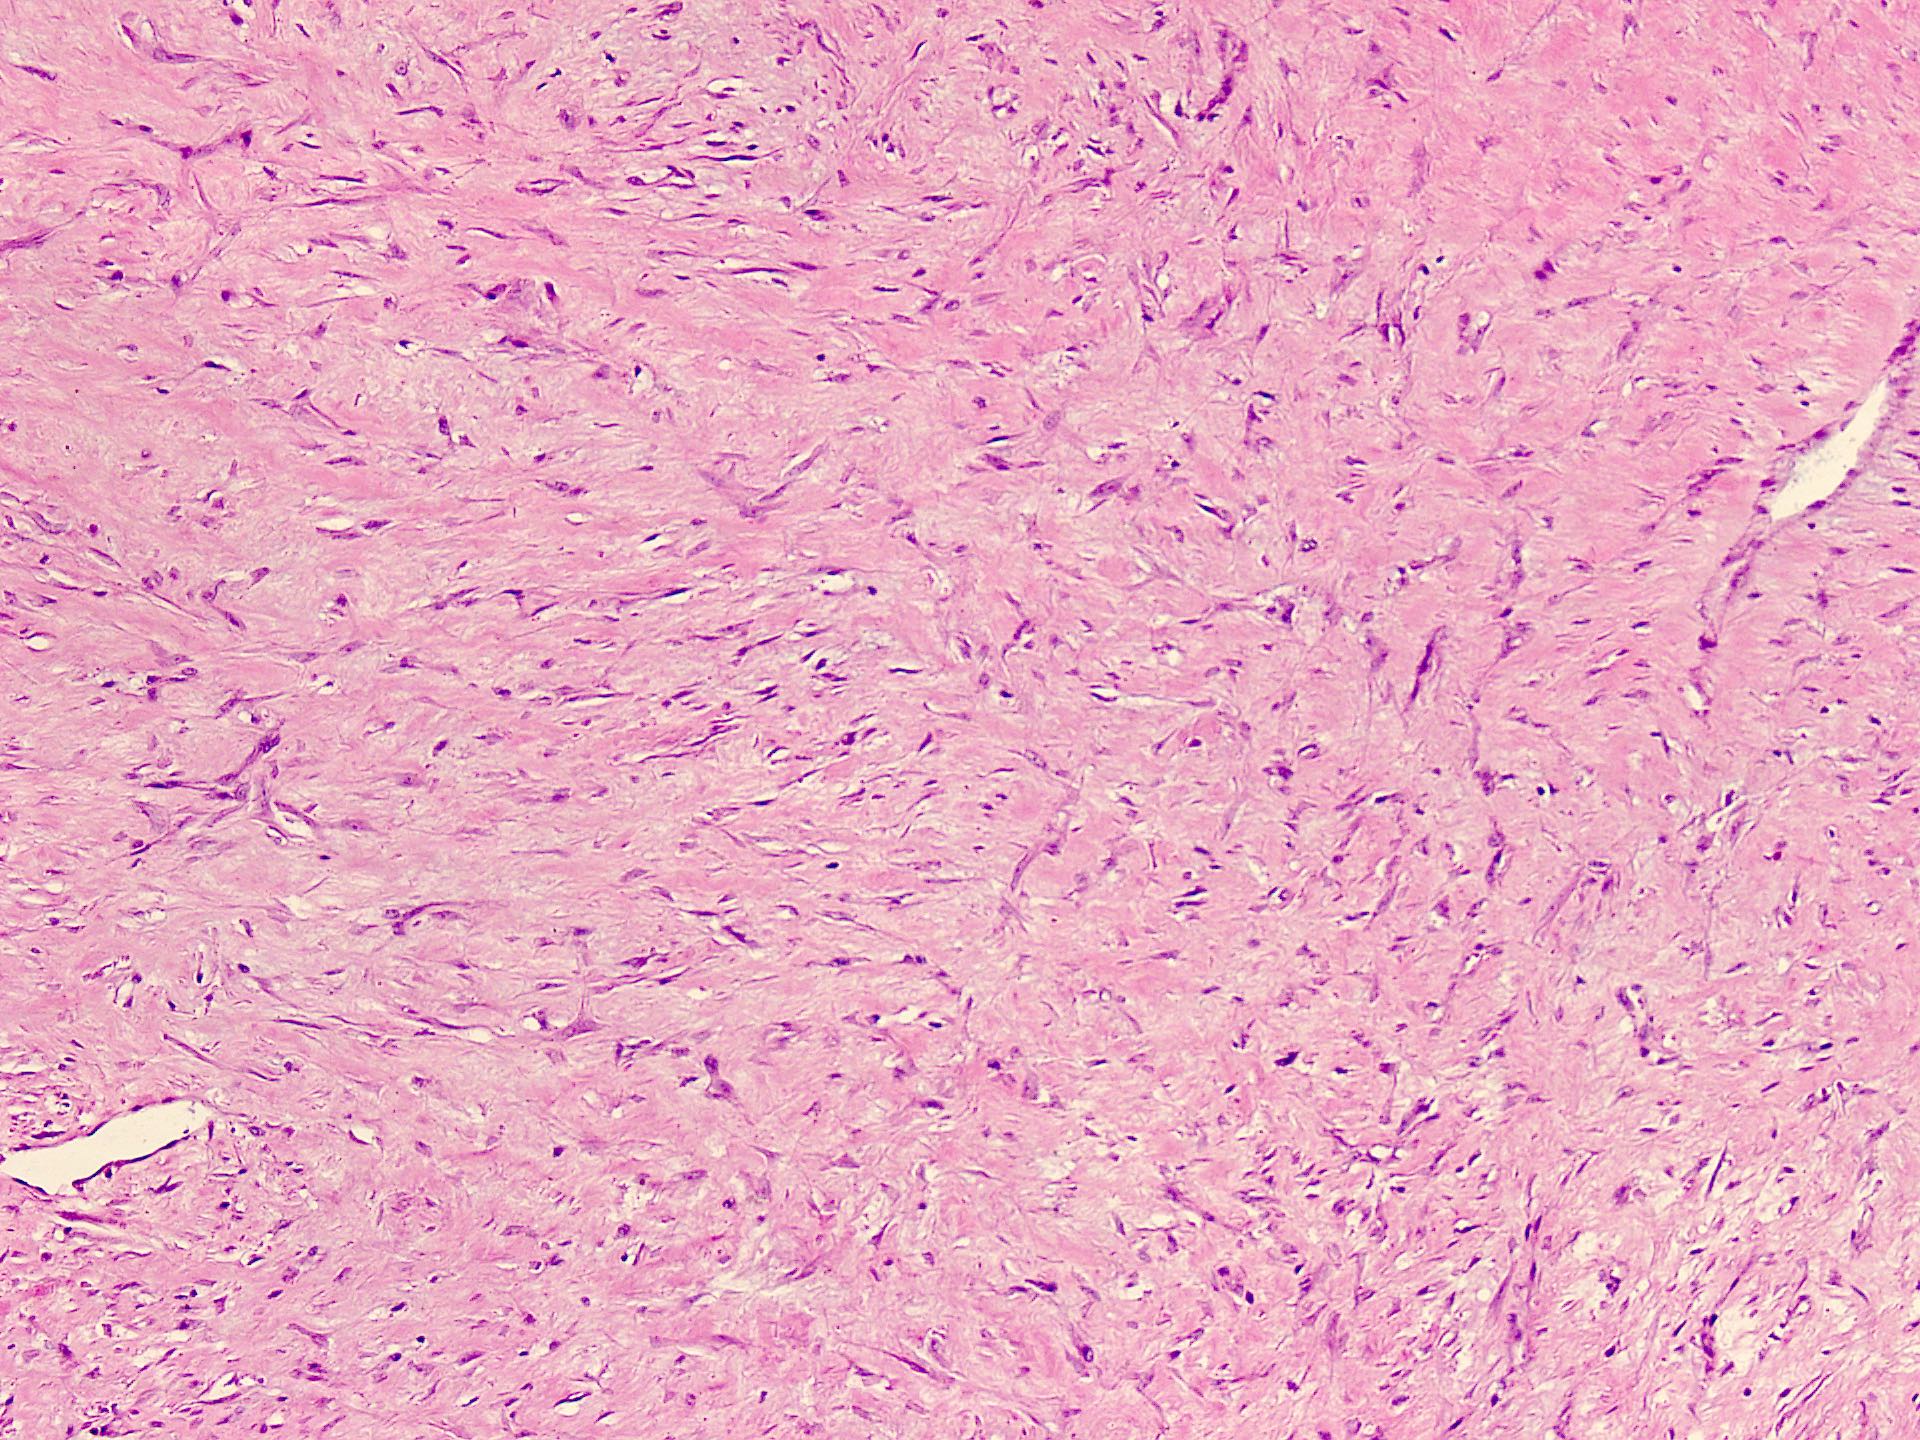

Microscopic (histologic) description

- Well circumscribed tumor of variable cellularity

- Cellularity mostly higher at tumor edges

- Bland spindle cells in a collagenous background

- Tumor has characteristic thin walled slit-like vessels

- Degenerative changes like myxoid / cystic change, osseous / chondroid metaplasia can be seen

- Bizarre pleomorphic cells can also be present

- Mitotically inactive

- Necrosis not present

- Cellular variant of fibroma of tendon sheath also exists; it overlaps morphologically with nodular fasciitis and fibrous histiocytoma (Cancer 1979;44:1945)

Microscopic (histologic) images

Contributed by Nasir Ud Din, M.B.B.S.

- Comment: Histology showed a well circumscribed, variably cellular lesion composed of bland spindle cells having regular nuclei arranged in sheets and fascicles. Thin walled vessels are present. The background is collagenous.

A 32 year old man has had painless swelling in the palm of his hand for 6 months. It was excised and the histology is shown in the above image. What is the most likely diagnosis?